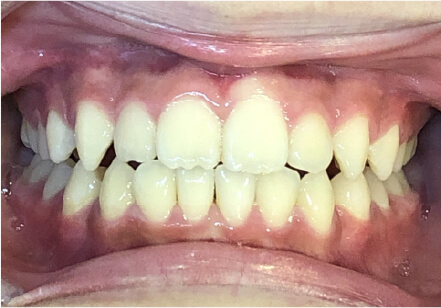

8歳

女性

前歯がでている、前歯が噛み合っていない

上下叢生、顎が狭いのでクリアコレクトで拡大配列+トレーニングで進めてく

全額アライナー矯正 クリアコレクト

リンガルアーチ使用

痛み・歯根吸収・歯肉退縮・虫歯・後戻り

924,000円、8ヶ月